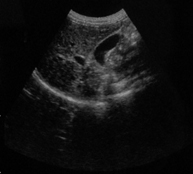

高清晰图像: